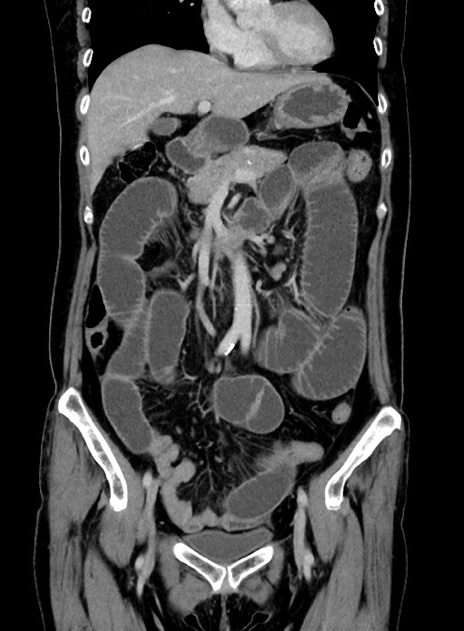

症例9(冠状断像)

【症例】 60歳代女性

【主訴】むかつき、みぞおちの痛み

【現病歴】3日前よりむかつきがあり、食事がとれない。

【既往歴】糖尿病

【身体所見】発熱なし、心窩部圧痛軽度あるも、腹膜刺激症状なし。

【データ】WBC 7400、CRP 1.92

横断像